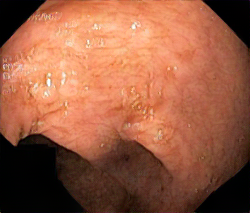

We have used a polyp dataset published with HyperKvasir dataset [51], which consists of polyp findings extracted from endoscopy examinations. HyperKvasir contains polyp images with corresponding segmentation masks annotated by medical experts. We use only this polyp dataset as a case study because of the time and resource-consuming training process of the SinGAN-Seg pipeline. However, the SinGAN-Seg model and pipeline can be used for any segmentation dataset.

A few sample images and the corresponding masks of the polyp dataset in HyperKvasir are shown in Fig 2. The polyp images are RGB images. The masks of the polyp images are single-channel images with white () for true pixels, which represent polyp regions, and black () for false pixels, which represent clean colon or background regions. In this dataset, there are different sizes of polyps. The distribution of polyp sizes as a percentage of the full image size is presented in the histogram plot in Fig 3, and we can observe that there are more relatively small polyps compared to larger polyps. Additionally, a subset of this dataset was used to prove that the performance of segmentation models trained with small datasets can be improved using our SinGAN-Seg pipeline, and the whole dataset was used to show the effect of using SinGAN-Seg generated synthetic images instead of a large dataset which has enough data to train segmentation models. In this regard, this dataset was used for two purposes: